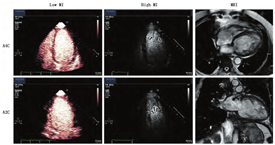

根据2014年ASE超声技师指南[38],VLMI指多脉冲消除序列技术,在MI<0.2时最为有效;低MI指MI<0.3的谐波显像技术,中等MI指MI为0.3~0.5的谐波显像技术,任何超过0.5的MI称为高MI。几乎所有市售超声显像仪均配有实时VLMI技术。这些脉冲序列方案可明显增强微泡在左室腔和心肌内的显示,改善RWM和MP分析。多脉冲VLMI显像的脉冲序列示意图已发表于2014年ASE超声技师指南的表1和图1[38]。脉冲反转(或称相位反转)是一种组织消除技术,可以传递极性交替(相位)的超声脉冲。虽然脉冲反转技术通过接收二次谐波,可以很好地抑制周围非心脏组织信号,提高图像的分辨力,但可以产生明显的信号衰减,特别是在心尖切面的心底心肌节段,衰减更为明显,部分原因是过滤了较高频率的谐波信号。功率调制(或称调幅)可发现基波以及谐波的非线性活动,当MI<0.2时,这些非线性活动几乎完全来自微泡的作用。此技术也称多脉冲消除技术,它改变每一脉冲的功率或幅度,而非极性。例如,当MI为0.05时,微泡和组织对超声脉冲的反应都是线性的,而当能量提高一倍时(0.1 MI),组织的反应仍然是线性的,但微泡的反应则是非线性的。来自两个不同脉冲(两倍幅度的0.05 MI和0.1 MI)的线性反应可互相减除,只显示来自微泡的非线性行为。虽然这种顺序方案可增强造影效果,但与脉冲反转或相位反转显像(仅检测较高频率的谐波反应)相比,理论上可能降低分辨力和图像质量。厂商也通过脉冲间相位和调幅,结合多脉冲技术这一较复杂的方式,进一步增强微泡在VLMI时的非线性活动,消除周围组织的线性反应。由于所需MI更低,VLMI与B-型低MI谐波显像相比,可以得到更好的组织消除,更强的信噪比,以及更少的微泡破坏[25]。VLMI显像技术总体的临床效应是提供较高空间分辨力、合理的时间分辨力,可以同时评估MP和RWM,这在检测冠状动脉疾病(CAD)特别重要(视频1和2,在www.onlinejase.com获取)。由于在基础频率下检测非线性活动,结合功率调制及脉冲间相位和振幅调制的脉冲序列方案,使衰减大为减少,微泡信号加强,心尖和心基底部节段显影大为改善(视频3和4,在www.onlinejase.com获取)。有关图像质量优化的具体说明,请参阅2014年ASE超声技师指南中的表2[38]。

无论是否结合间歇性高MI闪击脉冲去除心肌内增强剂,在使用UEA评估RWM(视频1,在www.onlinejase.com获取)以及LVEF的定量测定时,均应使用VLMI多脉冲显像技术(LVEF;COR IIa, LOE B-R)。

通过间歇性高MI闪击脉冲去除心肌内增强剂,分析心肌再灌注动力学和平台期心肌造影强度,VLMI多脉冲显像技术在评估MP(视频2-4;在www.onlinejase.com获取)时也非常有用(COR IIa, LOE B-R)。

虽然在2008年的ASE专家共识声明中就已经提到了VLMI多脉冲序列方案在多数系统上都可用[1],但最近才有制造商开始将它们用于LVO。VLMI技术最初是为心肌灌注评估而设计的,但它们对于微泡检测的敏感性和无漩涡伪影的心尖部心腔的完整造影显示对负荷LVO成像有很大的帮助。多中心和前瞻性单中心研究均证实了VLMI成像可以有效地检出RWM异常[16,45,66]。除了增强敏感性和心尖部的勾勒之外,VLMI技术还可检测负荷试验时透壁室壁增厚无法检出异常的心内膜下室壁增厚异常情况[42,66]。结合LVO以及高机械指数脉冲破坏后的心外膜层再充填过程有助于勾勒心内膜边缘和分析该处室壁增厚(图5和视频7;在www.onlinejase.com获取)。将UEA与VLMI成像用于室壁增厚和缺血的评估,并结合多巴酚丁胺负荷超声心动图对左束支传导阻滞患者进行常规评估,被证明可提高CAD的检出,并可独立预测死亡率和心血管事件[67]。

在进行DSE检查时,与单纯的室壁运动分析相比,心肌灌注分析提高了CAD的检出率。这似乎与缺血级联瀑布有关,在需氧增多性缺血期间,灌注异常出现在室壁运动异常之前[34]。正如前一节所述,导致VLMI成像灵敏度提高的另一因素是在使用灌注增强时检测心内膜下室壁增厚异常(图5)。这主要见于DSE检查中[42,45,66],虽然室壁增厚率可能看起来正常,但是心内膜下灌注缺损可揭示心内膜下室壁增厚异常(视频7;在www.onlinejase.com获取)。